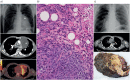

The diagnosis of a mediastinal mass may be challenging for clinicians, since lesions arising within the mediastinum include a variety of disease entities, frequently requiring a multidisciplinary approach. Age and sex represent important information, which need to be integrated with imaging and laboratory findings. In addition, the location of the mediastinal lesion is fundamental; indeed, we propose to illustrate mediastinal diseases based on the compartment of origin. We consider that this structured approach may serve as hint to the diagnostic modalities and management of mediastinal diseases. In this review, we present primary mediastinal tumours in the evolving context of new diagnostic and therapeutic tools, with recently described entities, based on our own experience with >900 cases encountered in the past 10 years.